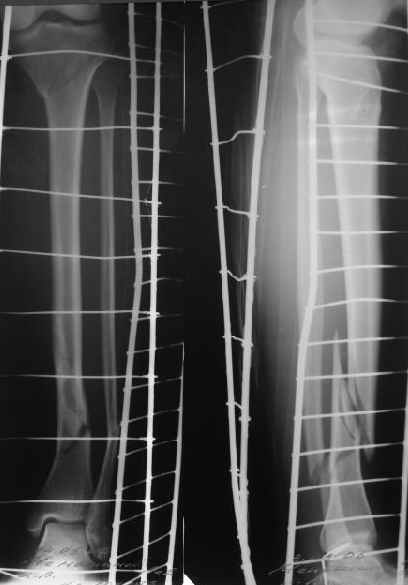

A typical case is attached, also an image with intra-op reduction obtained by a small wire distractor, in the moment of insertion a Poller wire in AP direction. Fixation by a SIGN nail. Despite the fibula was not fixed healing was obtained with the unchanged alignment.

In this particlar case 4 frontal wires were inserted in anterior and posterior aspects at both sides of proximal fracture, and fixed to a single half ring with some bend to provide compression with wire tension. Image attached.

На одной опоре, расположенной чуть дистальнее обычного, были закреплены 4 спицы, проведенные во фронтальной плоскости, по 2 в передней и задней части смежных фрагментов. Закреплены так, чтобы при их натяжении создалась компрессия. Картинка в приложении.